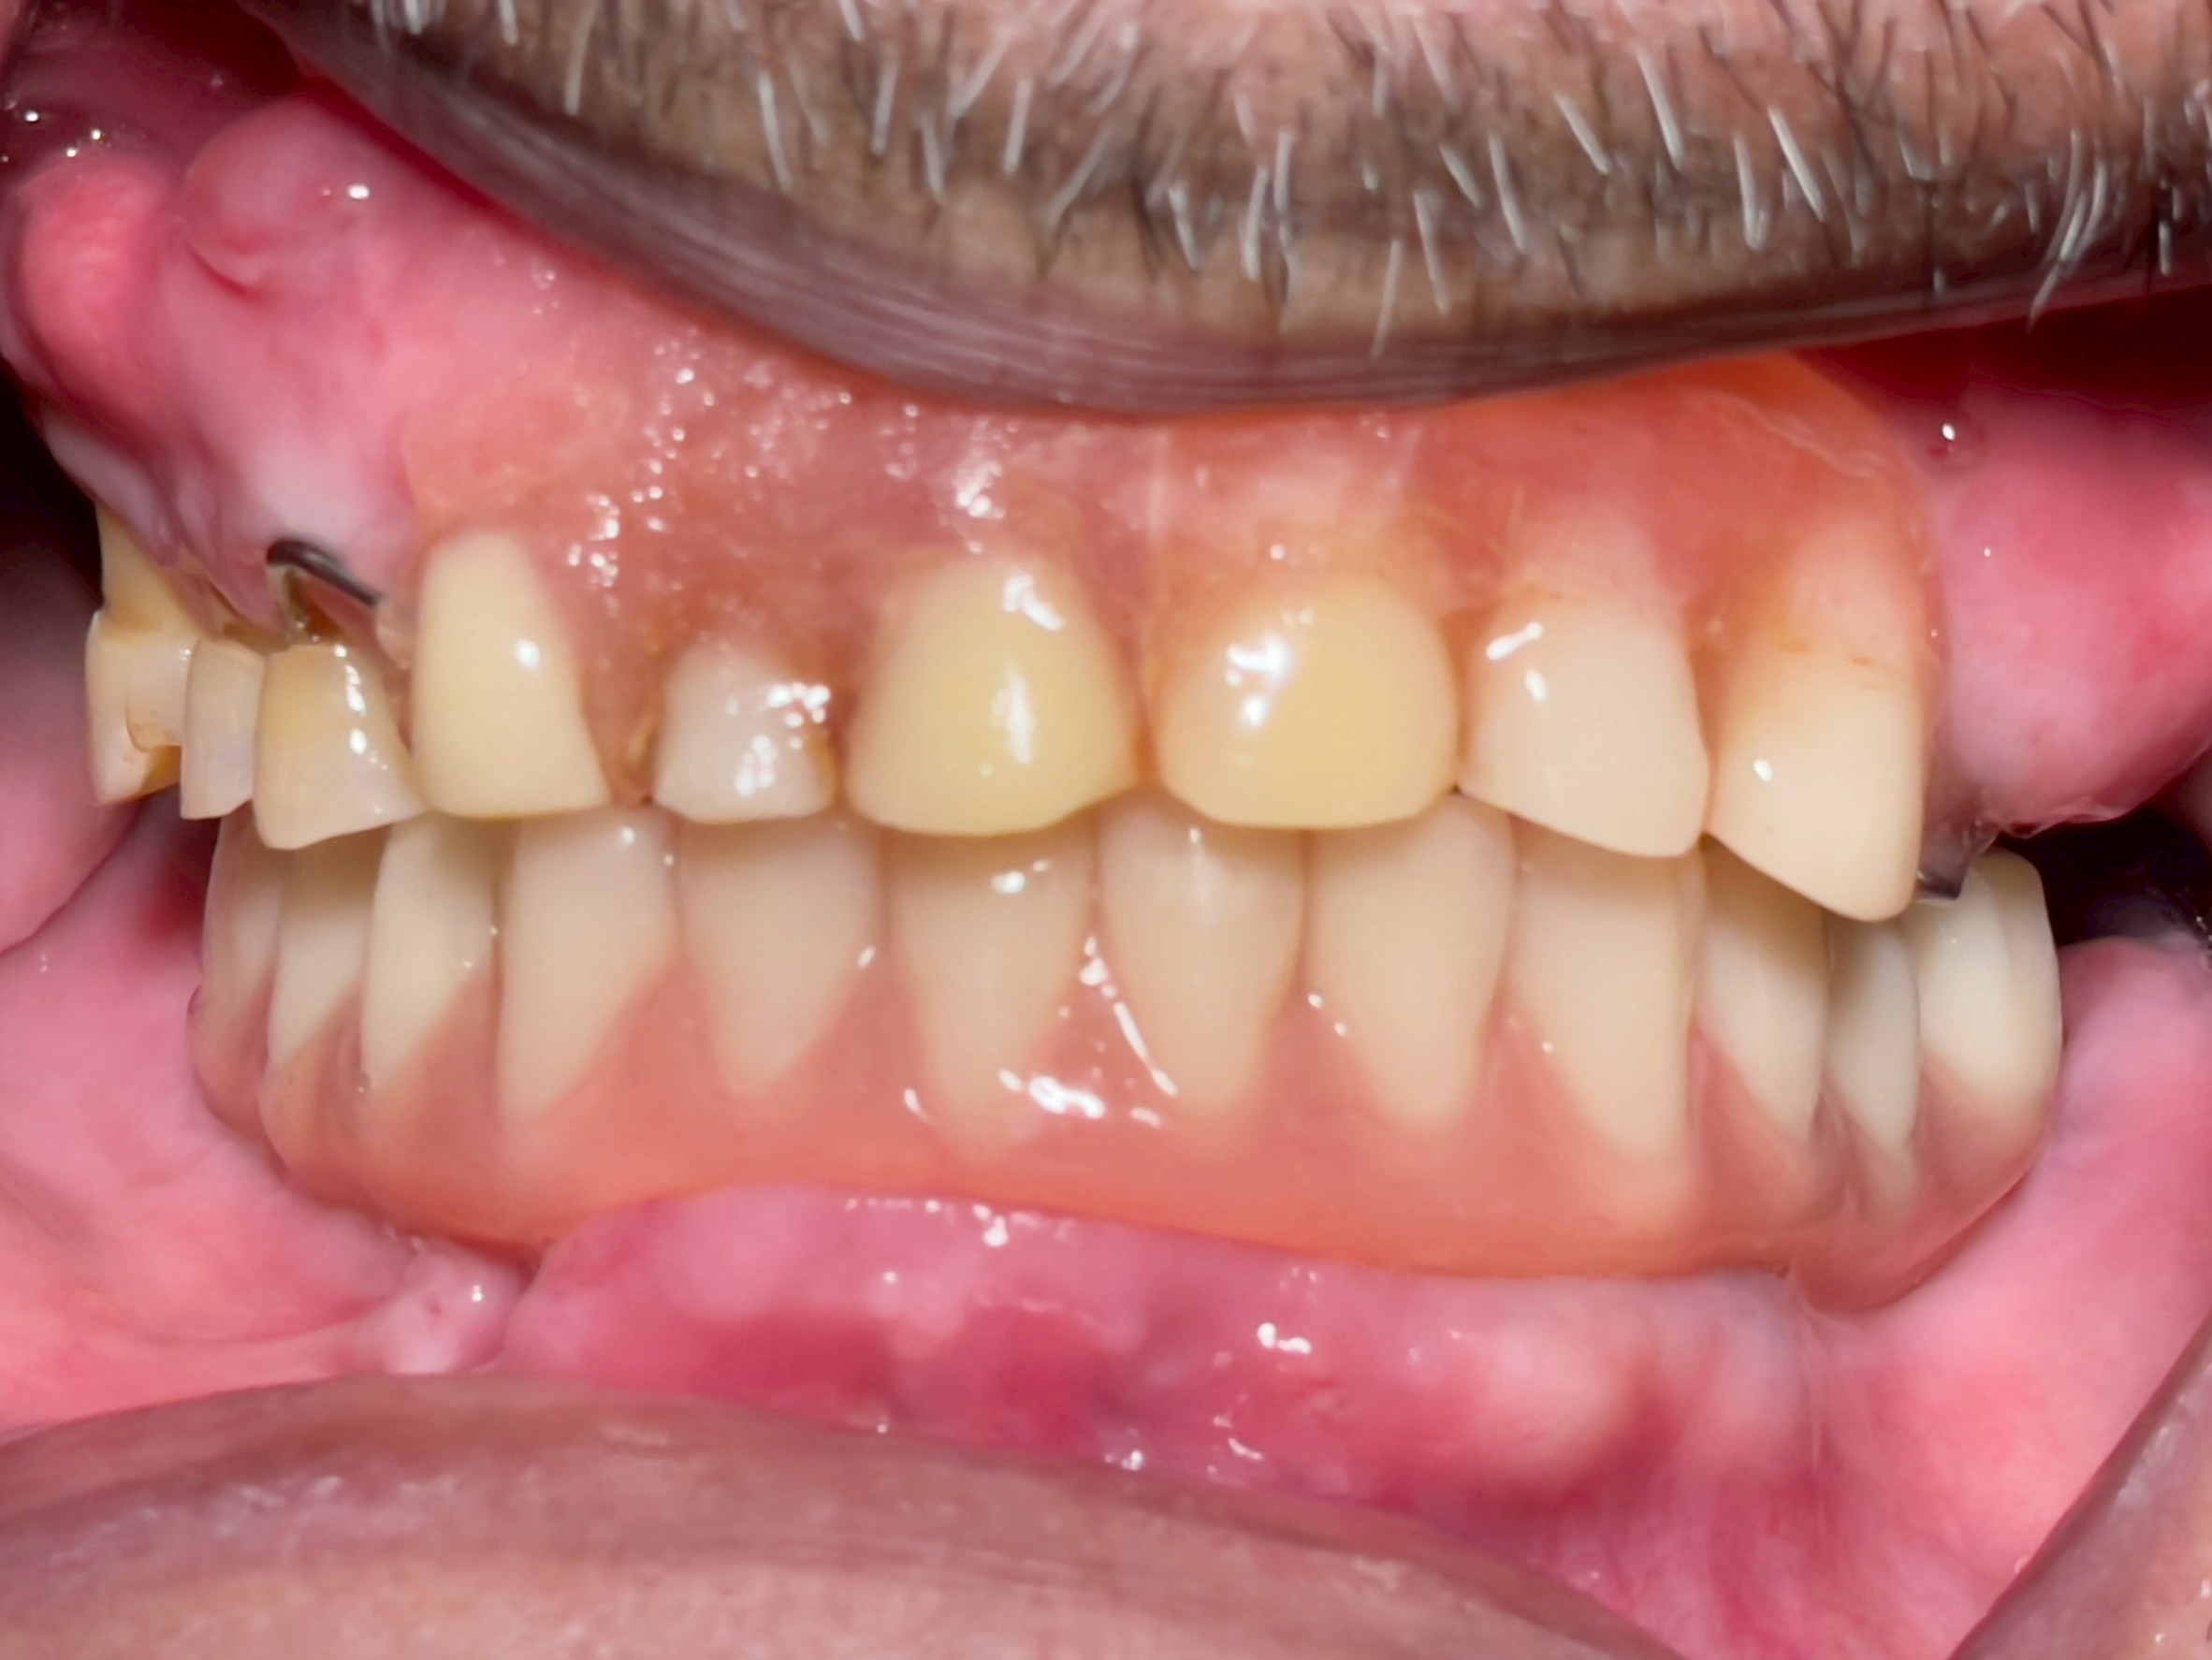

All-on-4 Implants Lower Jaw + Partial Denture Upper Jaw